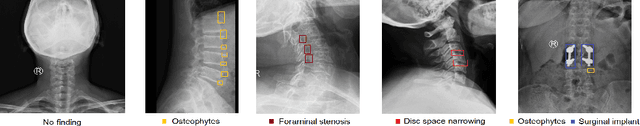

Abstract:Radiographs are used as the most important imaging tool for identifying spine anomalies in clinical practice. The evaluation of spinal bone lesions, however, is a challenging task for radiologists. This work aims at developing and evaluating a deep learning-based framework, named VinDr-SpineXR, for the classification and localization of abnormalities from spine X-rays. First, we build a large dataset, comprising 10,468 spine X-ray images from 5,000 studies, each of which is manually annotated by an experienced radiologist with bounding boxes around abnormal findings in 13 categories. Using this dataset, we then train a deep learning classifier to determine whether a spine scan is abnormal and a detector to localize 7 crucial findings amongst the total 13. The VinDr-SpineXR is evaluated on a test set of 2,078 images from 1,000 studies, which is kept separate from the training set. It demonstrates an area under the receiver operating characteristic curve (AUROC) of 88.61% (95% CI 87.19%, 90.02%) for the image-level classification task and a mean average precision (mAP@0.5) of 33.56% for the lesion-level localization task. These results serve as a proof of concept and set a baseline for future research in this direction. To encourage advances, the dataset, codes, and trained deep learning models are made publicly available.